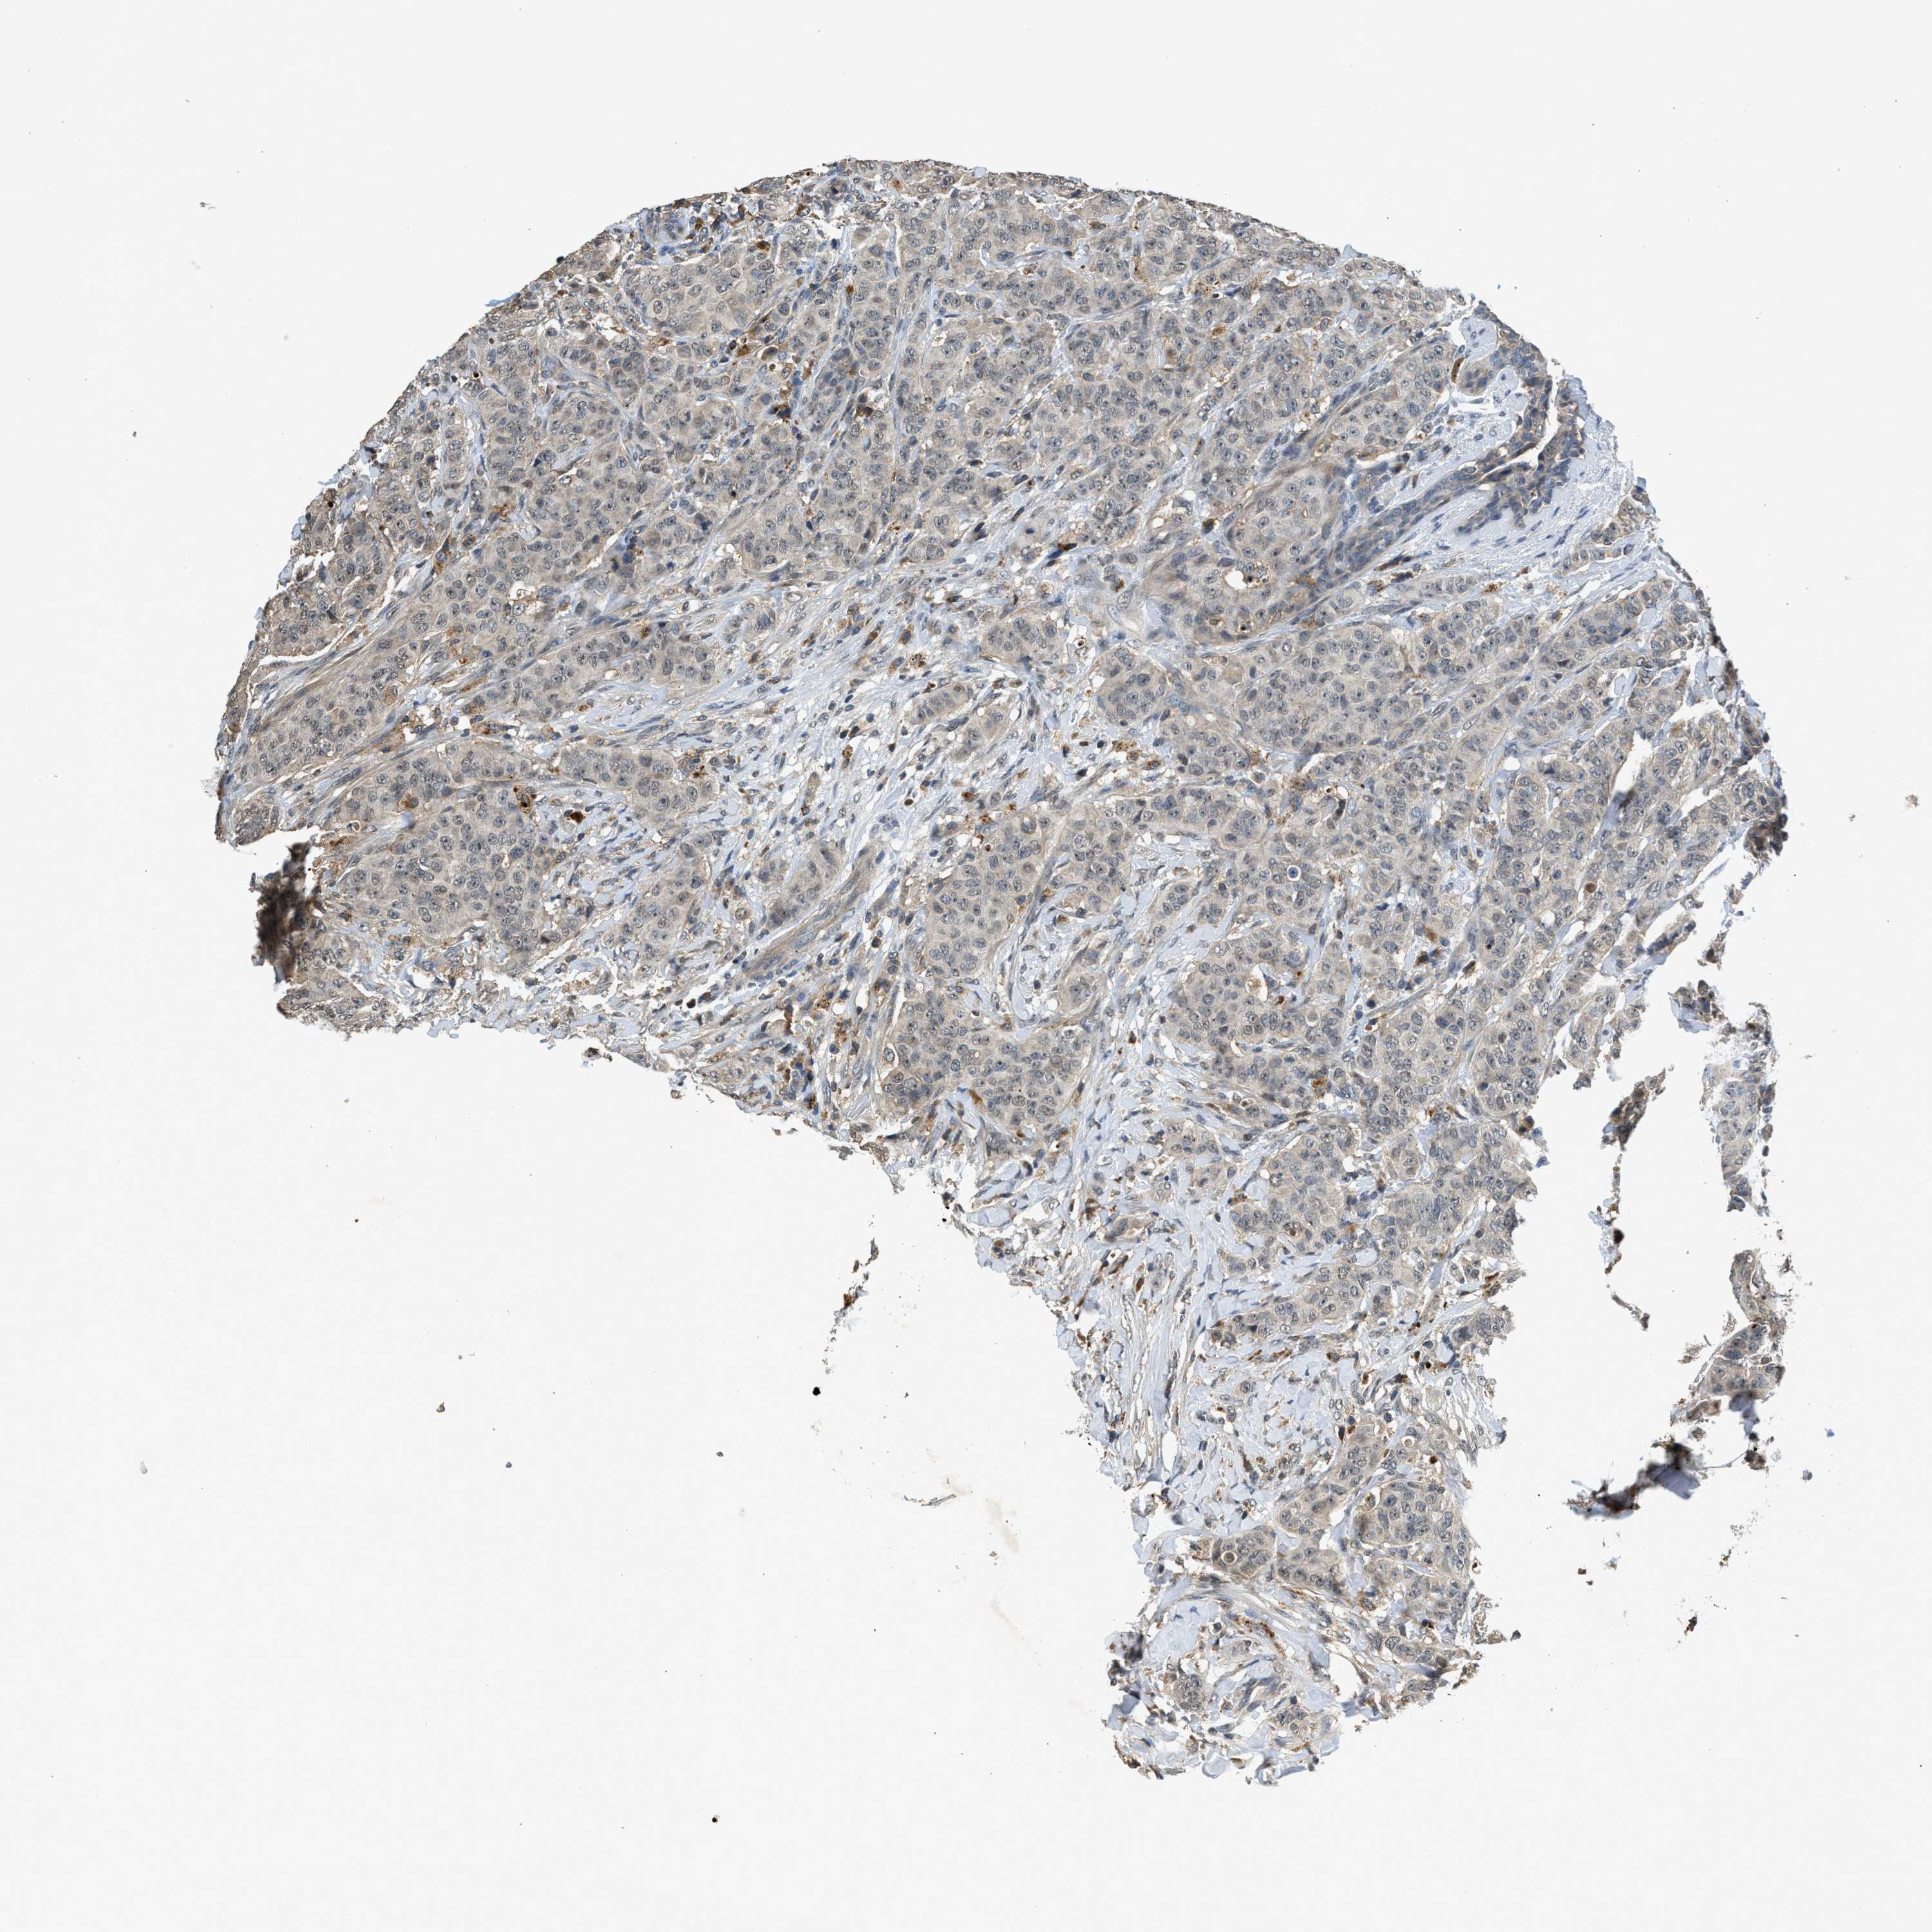

CANCER BREAST CANCER Show tissue menu

BRCA TCGA BRCA VALIDATION PROTEIN EXPRESSION